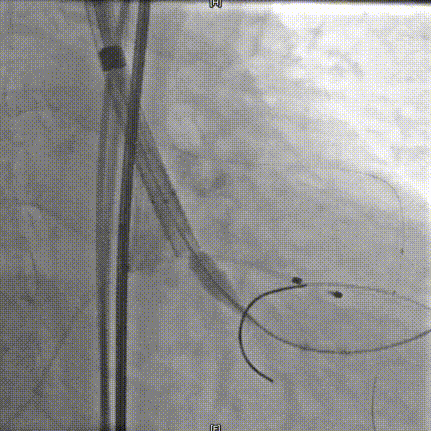

术中20mm球囊预扩可见轻微腰征,轻微瓣周漏,左冠充盈速度减慢,为保证患者安全,决定行冠脉保护,预防冠脉阻挡风险。选择AV26瓣膜,TaurusElite AV26瓣膜送至主动脉弓,输送系统轻松过弓及跨瓣,精准定位无冠窦最低点。

TaurusElite AV26瓣膜第一次释放定位位置接近瓣环,李怡教授准确定位判断,零位释放,瓣膜在手术计划的位置牢牢站稳了!手术过程行云流水,团队配合默契,操作细致熟练,主动脉根部造影及食道超声均只有少量瓣周漏;压差由术前的100mmHg直线下降到术后的5mmHg以内,TaurusElite首秀成功!